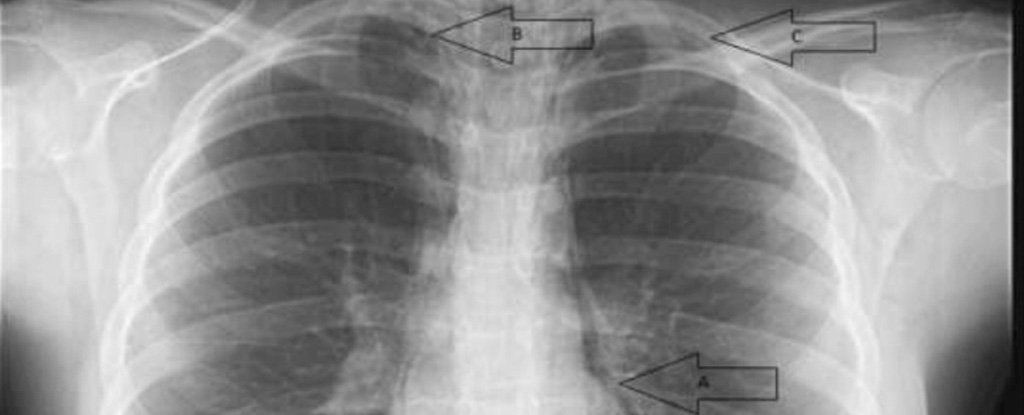

Seorang kanak-kanak berusia 16 tahun dari Texas terpaksa dikejarkan ke wad kecemasan apabila di dapati sesak nafas secara tiba-tiba.

Doktor segera melakukan pemeriksaan lanjut mendapati terdapat bunyi seakan-akan buih meletup di bahagian dada gadis itu setelah ditekan dengan jari.

Simptom yang dikenali sebagai ‘subcutaneus crepitus’, menunjukkan udara telah melalui tisu dibawah kulit pada bahagian dada nya. Apabila di tekan, buih udara kedengaran seperti meletup, menyebabkan bunyi pop terhasil.